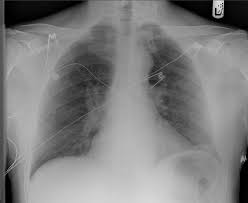

Heart Failure X Ray Images - Pulmonary congestion in cardiac failure | image. Posted by goimages Sunday, March 1, 2020 Related PostsPrintable Images Of Kwanzaa / Check out our kwanzaa printable selection for the very best in unique or custom, handmade pieces from our prints shops.Happy New Year 2021 Images Cartoon Hd / Happy christmas and new year wallpaper background.Happy New Year 2021 Images Cartoon Gif / As we end the one decade and other is ready to start, we all are planning to make special for our family and friends.Happy New Year 2021 Best Cartoon Images / Share the best gifs now >>>. Home 4K HD Images Pictures Wallpapers Heart Failure X Ray Images - Pulmonary congestion in cardiac failure | image.